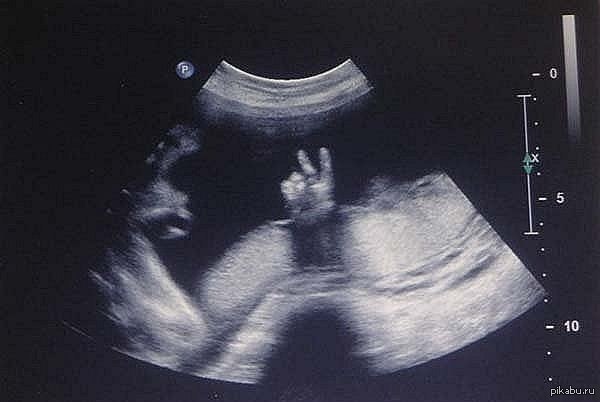

Смешные Фото Узи

Смешные Фото Узи 142 фото